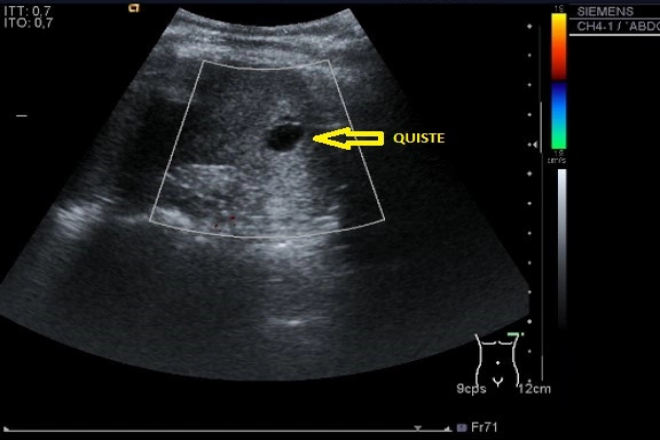

Ecográficamente, se observa una masa quística, puede ser de múltiples quistes con tabiques gruesos, dando la apariencia de “queso suizo”.

En TC, una masa bien definida quística, con una área central hipodensa.

Se trata de recién nacido a término, obtenido por vía cesárea, liquido amniótico con meconio, con antecedente de asfixia perinatal, el cual requirió reanimación e intubación. Durante su internamiento presenta alteración en pruebas de función hepática y hepatomegalia, se le realiza un usg es donde se observa a nivel de hígado una masa de 40×30 mm de aspecto heterogéneo, con vascularidad periférica, se hizo diagnostico de probable absceso hepático, vesícula biliar distendida con barro biliar e hidronefrosis. Se decidió administrar antibioticoterapia durante 15 días, y seguimiento ultrasonográfico semanal, en donde se observó el decremento de dicha masa, confirmando absceso hepático.